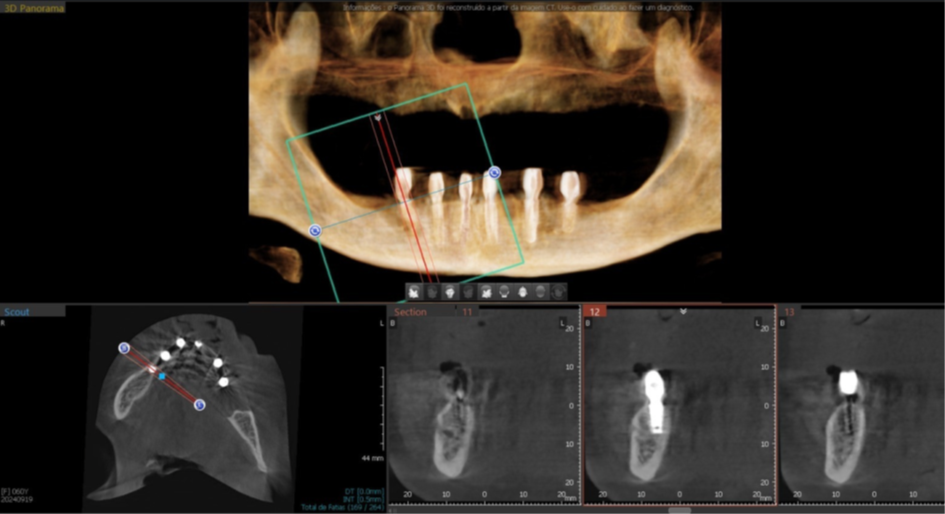

Figura 6 – Imagem do Raio-X panorâmico sem implantes e com marcações de guta-percha.

Figura 7 – Imagem do Raio-X panorâmico com planejamento digital dos seis implantes.

Figura 8 – Planejamento digital do implante 31.

Figura 9 – Planejamento digital do implante 33.

Figura 10 – Planejamento digital do implante 35.

Figura 11 – Planejamento digital do implante 41.

Figura 12 – Planejamento digital do implante 43.

Figura 13 – Planejamento digital do implante 45.

Foram planejados seis implantes nas seguintes medidas: elemento 31: 3.5x11mm; elemento 33: 3.5x11mm; elemento 35: 3.5x7mm; elemento 41: 3.5x11m; elemento 43: 3.5x11mm; elemento 45: 3.5x7mm; que foram distribuídos ao longo da mandíbula. O planejamento virtual do guia cirúrgico foi realizado em parceria com a empresa TechnoGuide, sendo posteriormente validado e aprovado para a confecção do guia definitivo.